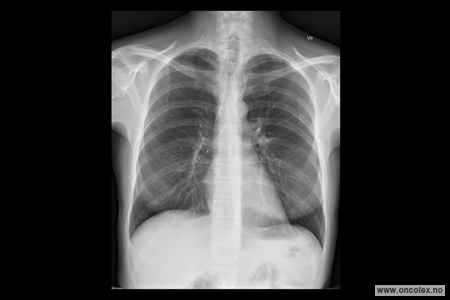

Røntgen toraks er en røntgenundersøkelse som tas for å se på lunger, hjerte og lymfeknuter i brystskilleveggen mellom lungene.

Hensikten med undersøkelsen er å stille diagnose, kartlegge sykdommens utbredelse, kontrollere forholdene i lungene før en eventuelt operasjon, eller vurdere effekten av behandlingen. Ved spesielle problemstillinger vil eventuelle spesialbilder bli tatt.

Under bildeopptaket står pasienten i en bestemt stilling foran røntgenapparatet.

Det tas bilder i front og fra siden.

Strålene som passerer gjennom kroppen treffer en sensor på den andre siden.

Røntgenbildet viser skjelett og lunger tydelig.